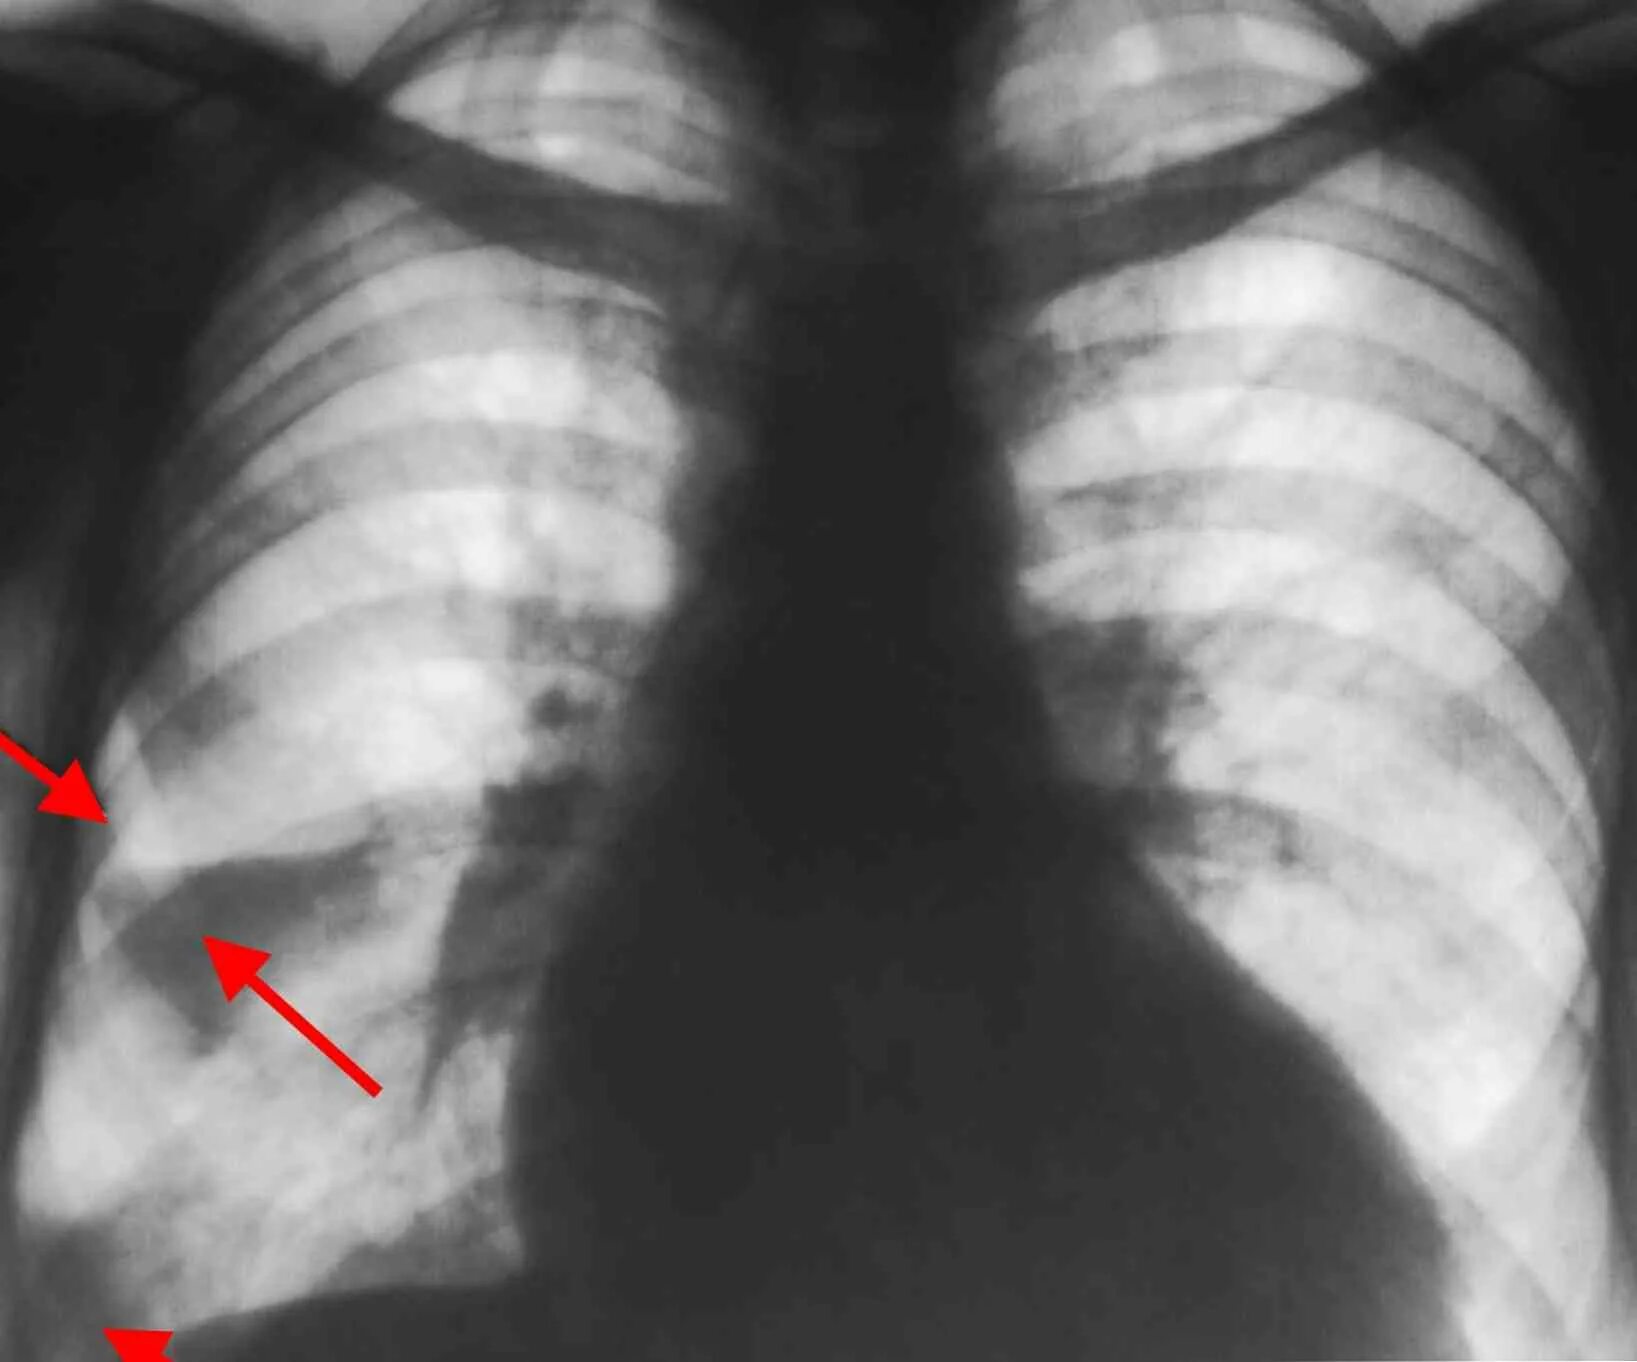

Аортокоронаросклероз легких что это такое